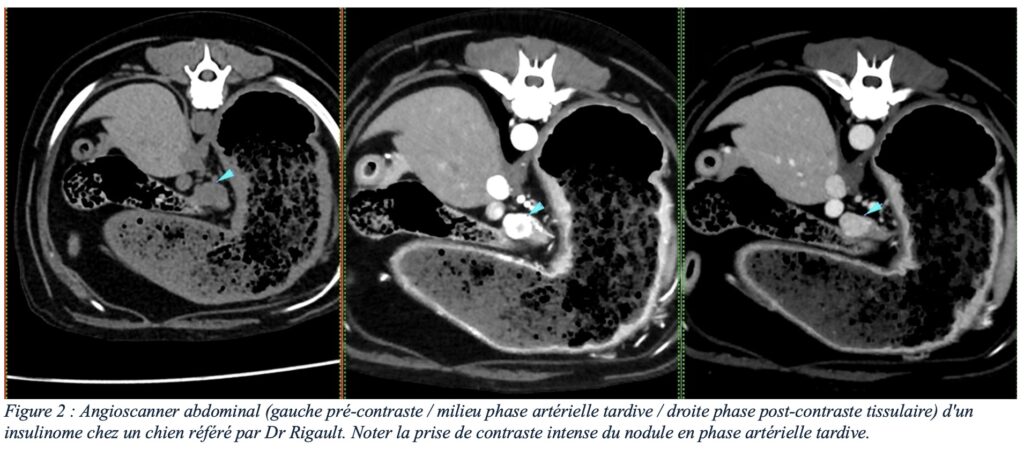

Le scanner, et plus particulièrement la phase artérielle tardive d’un angioscanner (3) (figure 2), est un examen présentant une sensibilité nettement supérieure à l’échographie (4). En effet, les insulinomes et leurs métastases présentent un rehaussement intense et précoce après injection intraveineuse de contraste iodé, permettant une détection plus fiable des insulinomes et leurs éventuelles métastases (bien que des faux positifs soient possibles), tout en s’affranchissant des limites liées au gabarit de l’animal (figures 3 et 4). Les angioscanners peuvent être effectués manuellement, mais les injecteurs automatiques de contraste facilitent la partie technique de cet examen (figure 5).